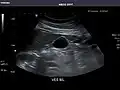

Abdominal Ultrasound (Full Exam)

STRUCTURED REPORT

(Technique: Transabdominal ultrasonography; Device: Toshiba Aplio XG)

Kidneys: Right and left kidneys measure 11.5 cm and 12 cm in length respectively. No hydronephrosis. Small left lower pole kidney cyst.

Left kidney -